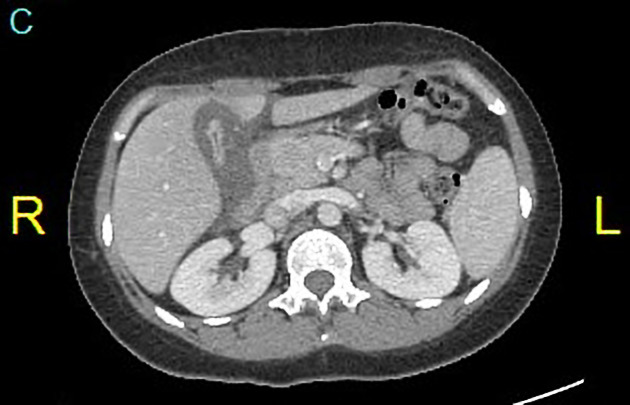

CT Scan menawarkan gambaran yang lebih mendetail mengenai potongan melintang organ hati dari berbagai sudut pandang.

Teknologi ini sanggup memperlihatkan sebaran tumor, lokasi pendarahan, atau tingkat keparahan sirosis secara sangat presisi.

Dokter radiologi membaca hasil foto ini untuk menentukan langkah pengobatan yang paling sesuai bagi kebutuhan pasien.